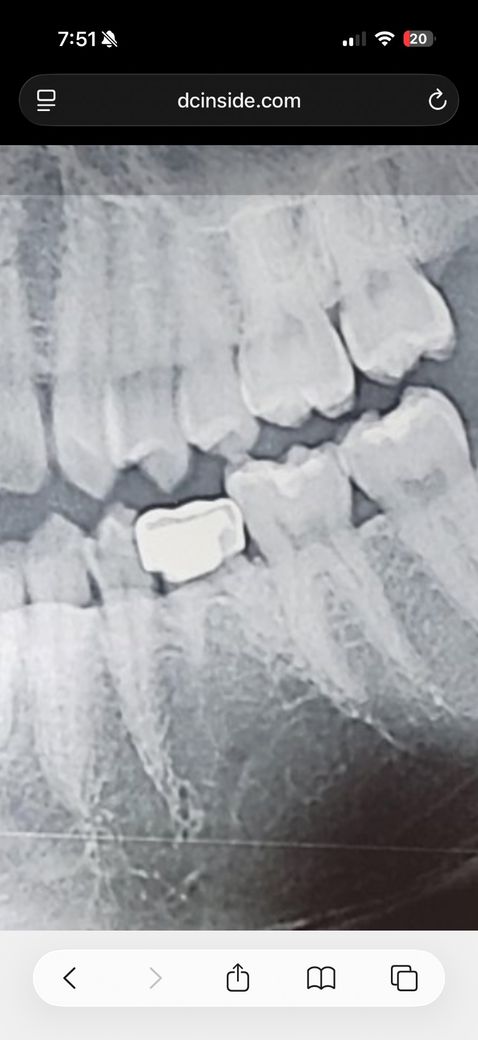

크라운씌운곳에서 입냄새가 너무나요

2년전부터 입냄새가 심해졌다고 주변에서 말해줘서 알게됐어요. 10개월전에 크라운을 씌었는데 크라운쪽에 손을대고 냄새를 맡아보니 진짜 냄새가 심해요. 치과에서는 임플란트를 얘기하는데 임플란트해야될까요?

크라운 하방으로 충치가 진행되어 있어보이며 선천적으로 영구치가 결손되어 있는 것 같습니다.

사진상에 보이는건 유치인거 같습니다. 불편하시면 발치후 임플란트를 하시는게 좋을것같습니다.

사진으로 보이는 치아는 유치를 사용하는것으로 보입니다. 상부 크라운 내부로 충치가 생겨 이물질이 들어가고 부패가 되면 냄새가 나게 됩니다.

유치의 경우 뿌리가 짧기 때문에 충치등으로 인해서 유지가 되지 않는다면 발치를 하고 임플란트를 하는것이 좋을수 있습니다.

첨부된 사진이 크라운 씌운거라면 그 치아는 유치입니다

영구치는 결손치인 상태이므로 유치를 쓸때까지 쓰고 나중에 뺀뒤 임플란트를 심거나 아니면 브릿지를 할수밖에 없는데요

크라운 씌운 내부에 이차우식이 있어 냄새가 나는 것 같습니다